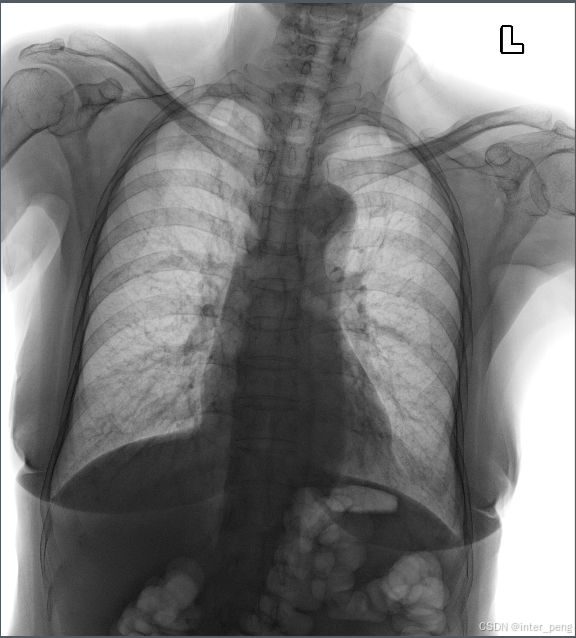

近日遇到了某家医院的一些胸部DR的图像.用一般的dicom软件打开后,显示是反片状态.

也就是,高密度区域是黑色; 低密度区域是白色.

这个和一般的DR, CT图像,是相反的.

一般的DR, CT图像,由于背景是空气,密度比较低,所以呈现为黑色; 有器官,肌肉和骨骼的地方,都是亮色, 即不同程度的白色.

输入图像: